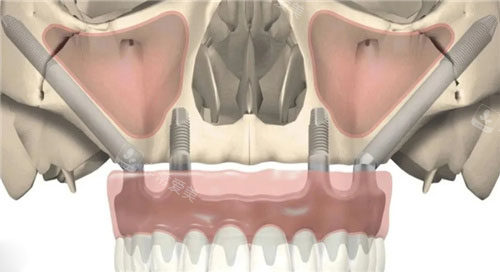

穿颧穿翼种植材料

口腔穿颧穿翼

穿颧穿翼种植牙示意图

穿颧穿翼种植正面图

穿颧穿翼种植分区图解